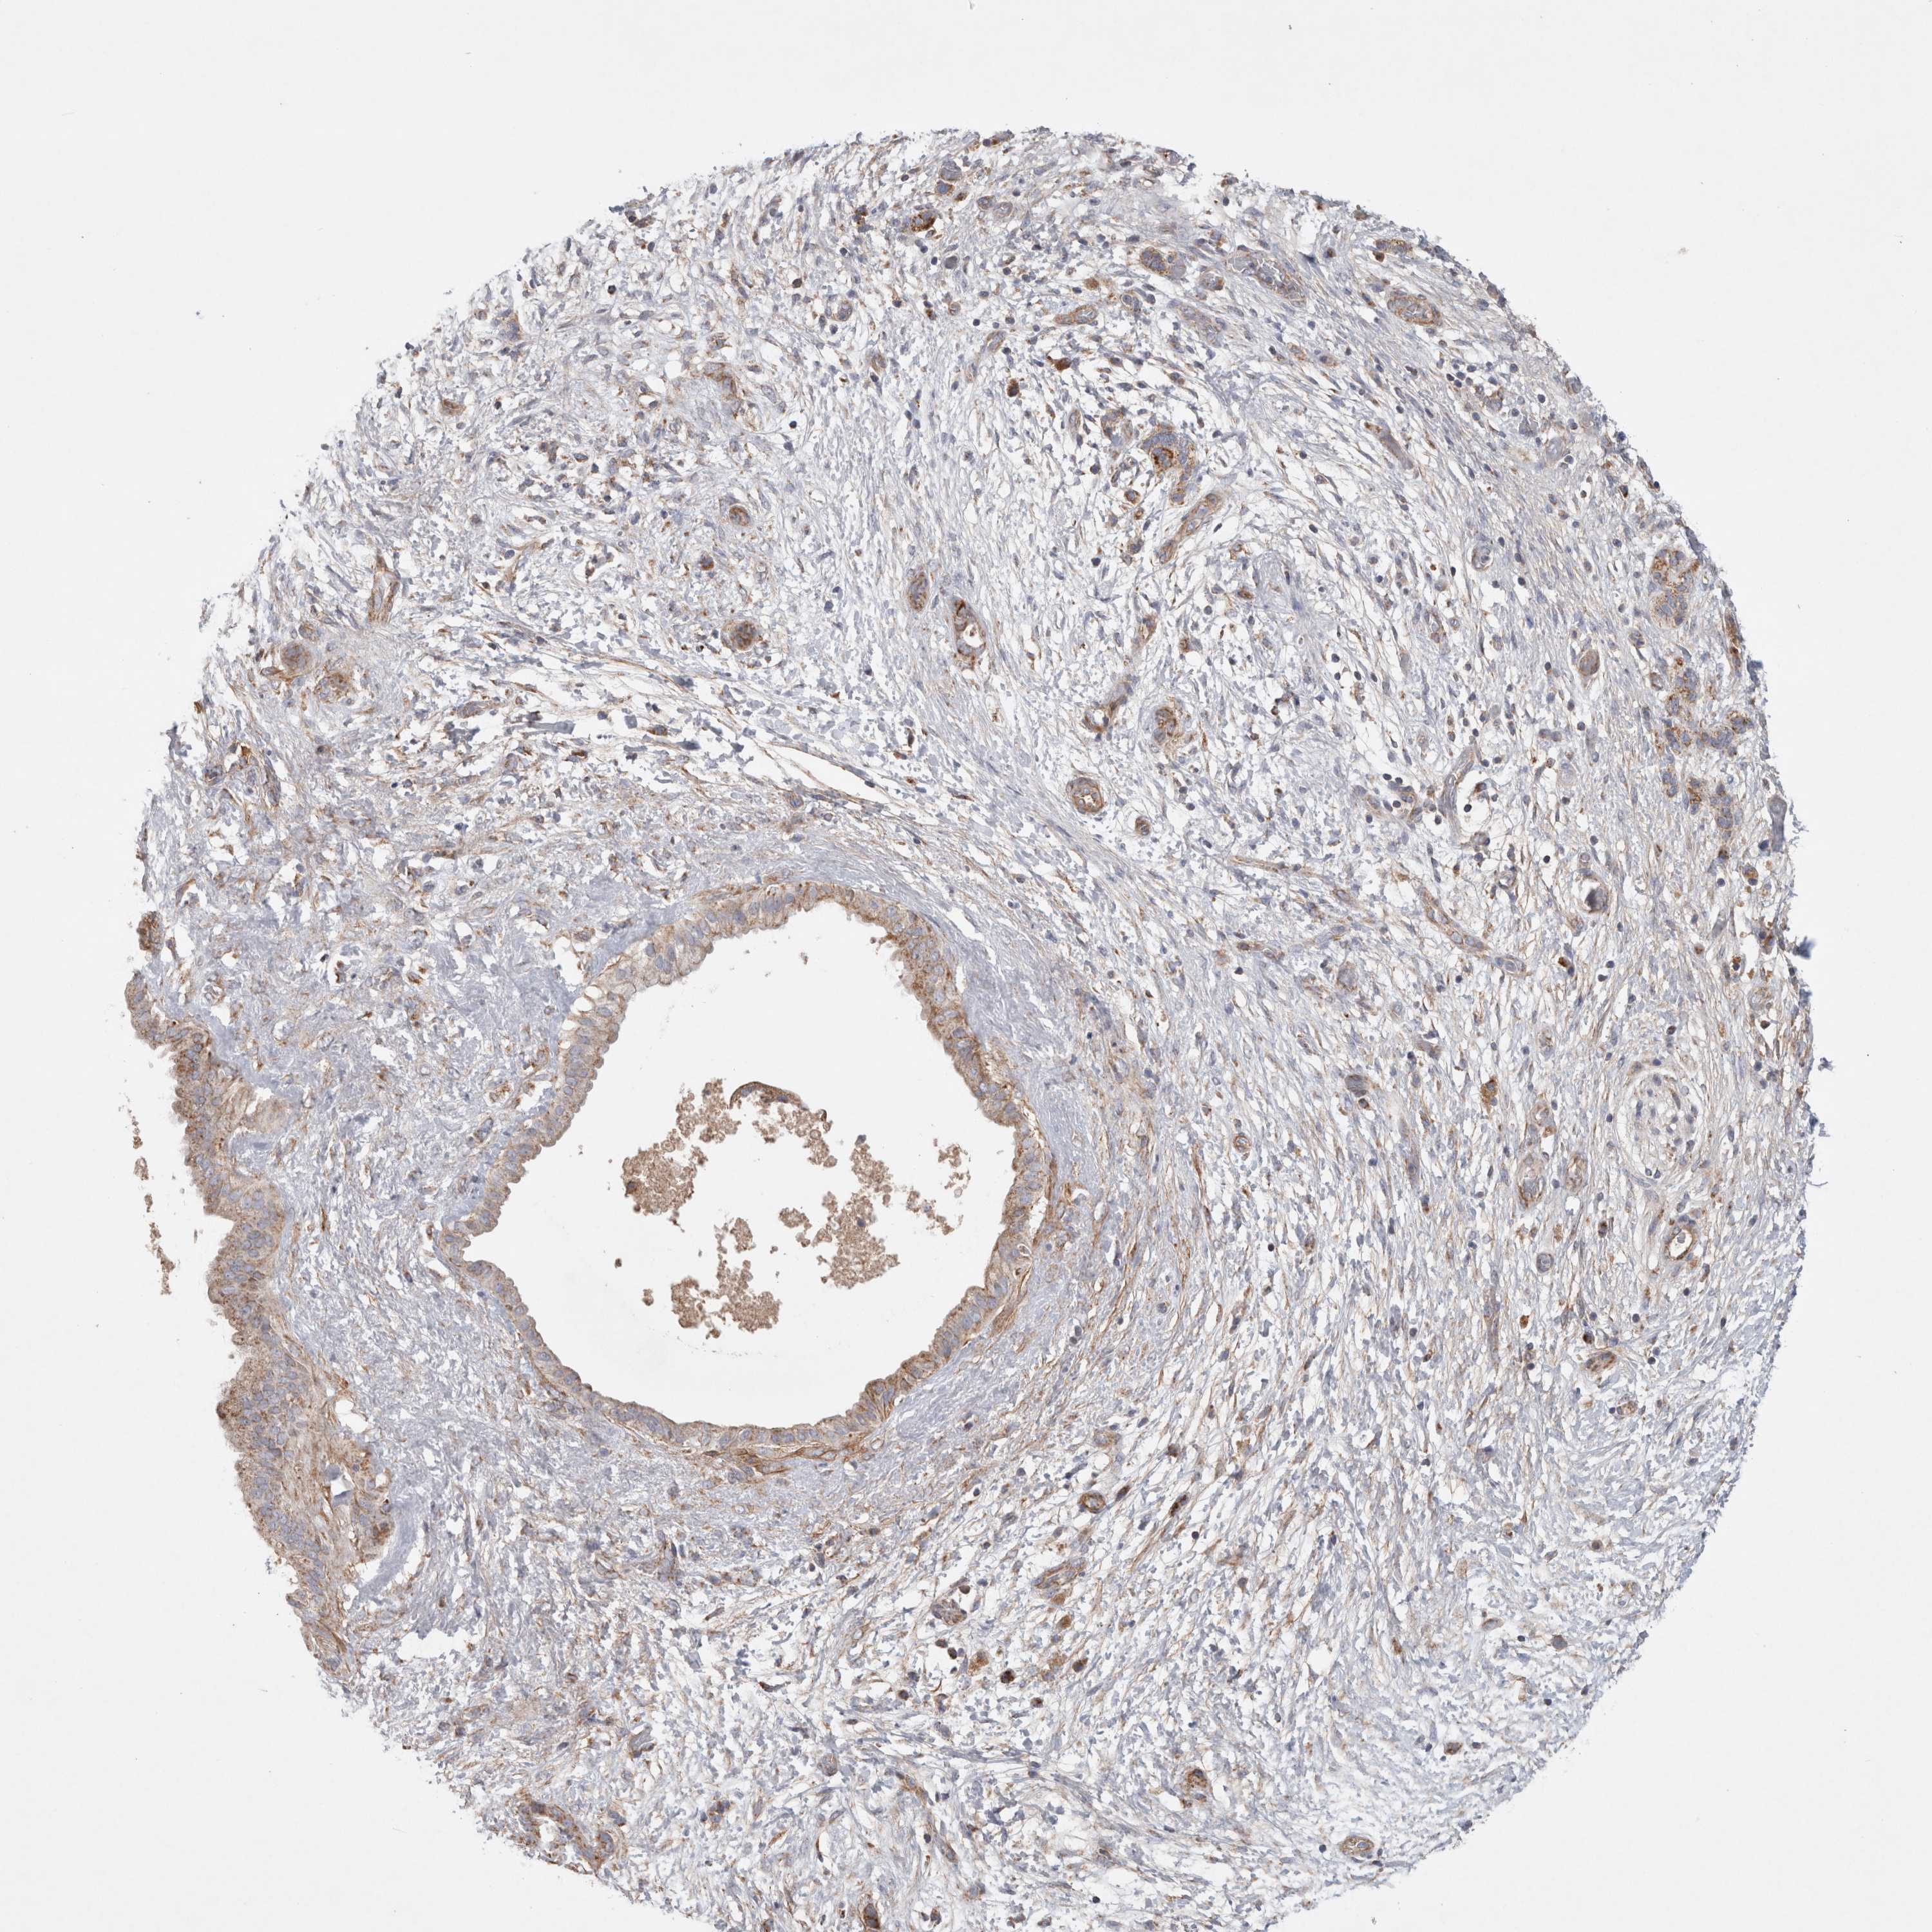

PANCREATIC CANCER - Protein expressioni

A mouse-over function shows sample information and annotation data. Click on an image to view it in a full screen mode. Samples can be filtered based on level of antibody staining by selecting one or several of the following categories: high, medium, low and not detected. The assay and annotation is described here.

Note that samples used for immunohistochemistry by the Human Protein Atlas do not correspond to samples in the TCGA dataset.

Antibody stainingi

Antibody staining in the annotated cell types in the current human tissue is reported as not detected, low, medium, or high, based on conventional immunohistochemistry profiling in selected tissues. This score is based on the combination of the staining intensity and fraction of stained cells.

Each image is clickable and will lead to virtual microscopy that enables deeper exploration of all samples and also displays staining intensity scores, fraction scores and subcellular localization as well as patient and tissue information for each sample.

Antibody HPA027202

Staining

High

Medium

Low

Not detected

Intensity

Strong

Moderate

Weak

Negative

Quantity

>75%

75%-25%

<25%

None

Location

Nuclear

Cytoplasmic/membranous

Cytoplasmic/membranous,nuclear

Adenocarcinoma, NOS